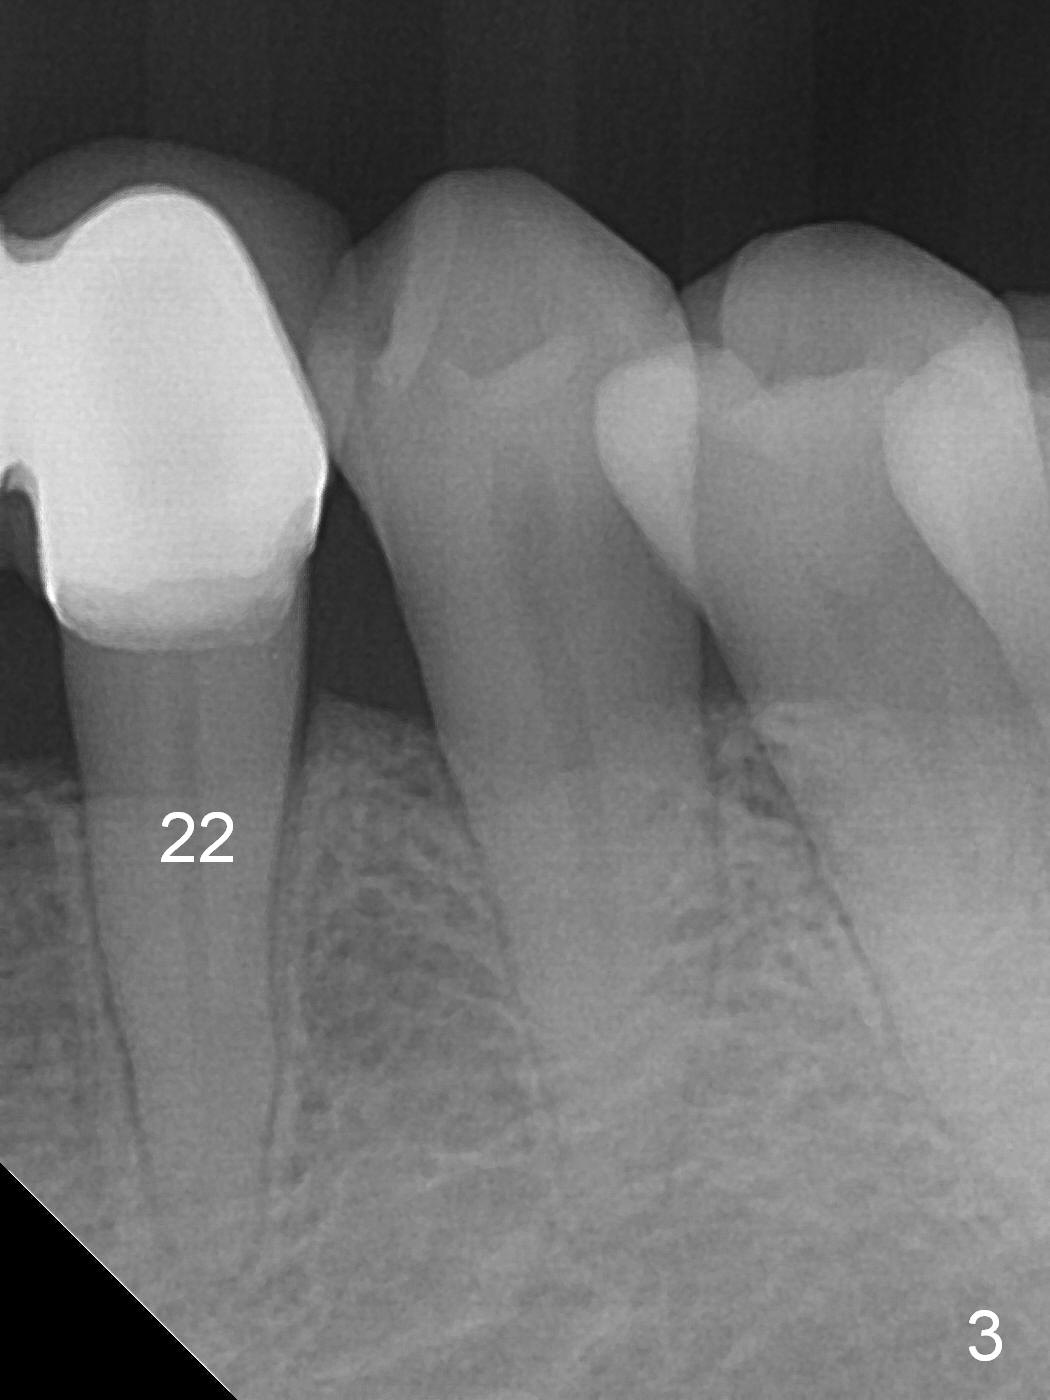

For the same token (severe bone loss at the mesial aspect of the site of #27), the site of #26 is not a good candidate one for implantation (Fig.2 *). The site of #25 is most likely a better one. The site of #23 should be the most favorite one among #23-26, since the edentulous site next to the dentate one is less likely resorbed after extracted. For a FPD, abutments should be far away from each other. No matter what, prepare 1-piece implants (as small as 2.5 and 2.0 mm ones) and surgical handpiece (why?). Take preop photos to show recessive gingiva at #27.